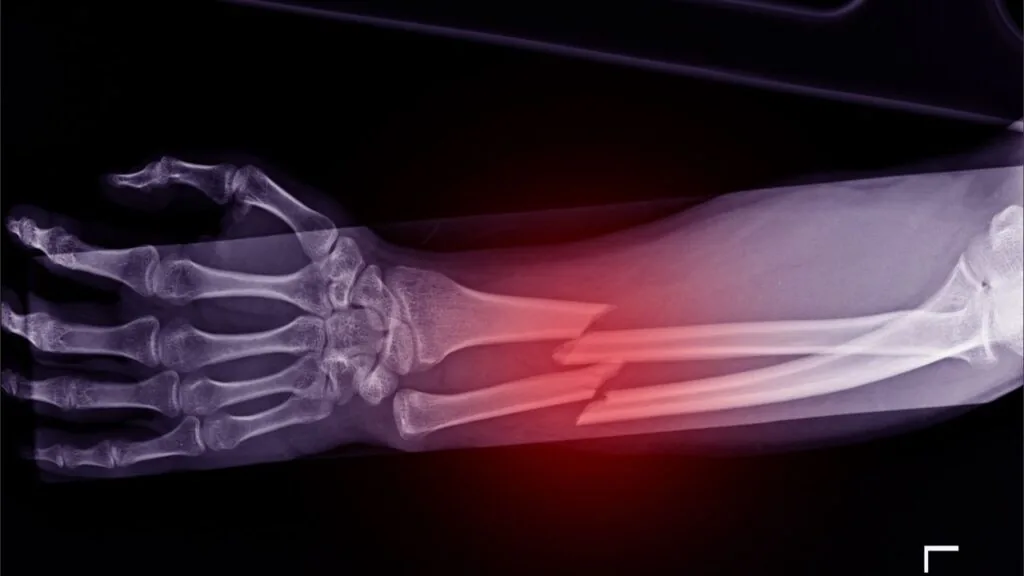

O tempo varia conforme a complexidade da lesão e a clareza das provas que você apresenta. Por exemplo, provar sequelas de fratura de tíbia e fíbula costuma ser mais rápido porque o Raio-X mostra tudo claramente: o osso colou torto ou tem parafusos limitando o movimento.